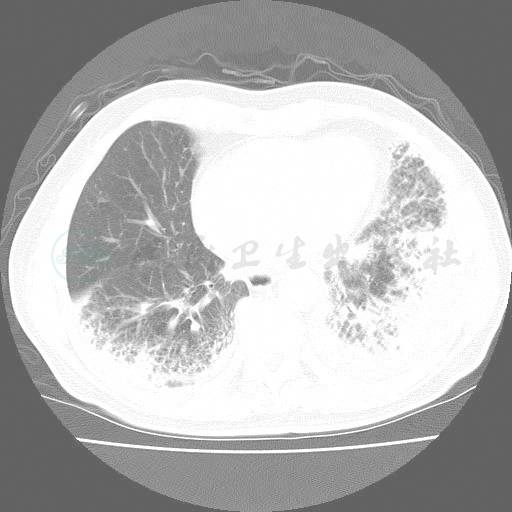

WBC 22.38×109/L,N 85.7%,血沉105mm/h,C反应蛋白129.2mg/L,类风湿因子47IU/ml,肝肾功能正常。动脉血气(吸氧2L/min):pH 7.451,PaCO2 32.33mmHg,PaO2 60.15mmHg,HCO3- 22.0mmol/L。5次痰涂片找抗酸杆菌,3次痰涂片找真菌,2次痰细菌培养,真菌培养均阴性。血清隐球菌夹膜多糖抗原乳胶凝集试验、曲霉抗原半乳甘露聚糖试验(GM试验)、真菌1,3-β-D葡聚糖抗原(G试验)阴性。血结核杆菌抗体、支原体、衣原体、军团菌抗体阴性。HIV抗体阴性。自身抗体十项、ANA、ANCA阴性。胸部HRCT(2008-3-25):双肺间实质性炎症,左侧少量胸腔积液(图1)。

图1 两肺呈不规则条索、斑点及网格状影,两下叶容积缩小,左侧少量胸腔积液